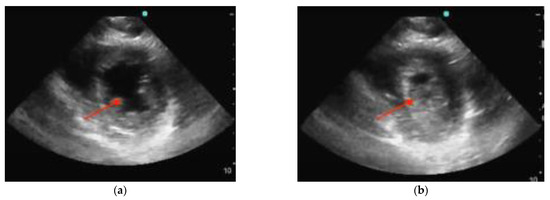

3.4.1. Cardiac Tamponade